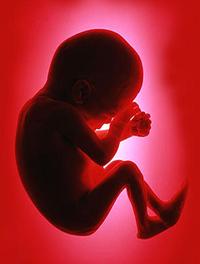

Du nouveau en biométrie fœtale !

Chaque année, plus de 800 000 grossesses sont suivies en France. Au cours des 3 échographies réalisées pour leur suivi, ce sont pratiquement 10 millions de mesures (LCC, BIP, PC, PA et LF) par an qui sont donc réalisées. Le dépistage des fœtus petits pour l’âge gestationnel (PAG) et en retard de croissance intra-utérin (RCIU), ou au contraire des fœtus macrosomes, est la première raison de la réalisation de ces mesures (1).

Il est donc essentiel pour apprécier ces mesures, [...]